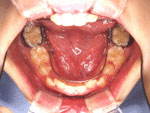

- 昔は歯の表面に金属のバンドをつけました。かなり目立ち本人にも違和感がありました。

- しかし、現在は歯の白さとほとんど変わらないセラミック製の装置で大きさも小さくよほど大きく口を開けない限りほとんどわかりません。